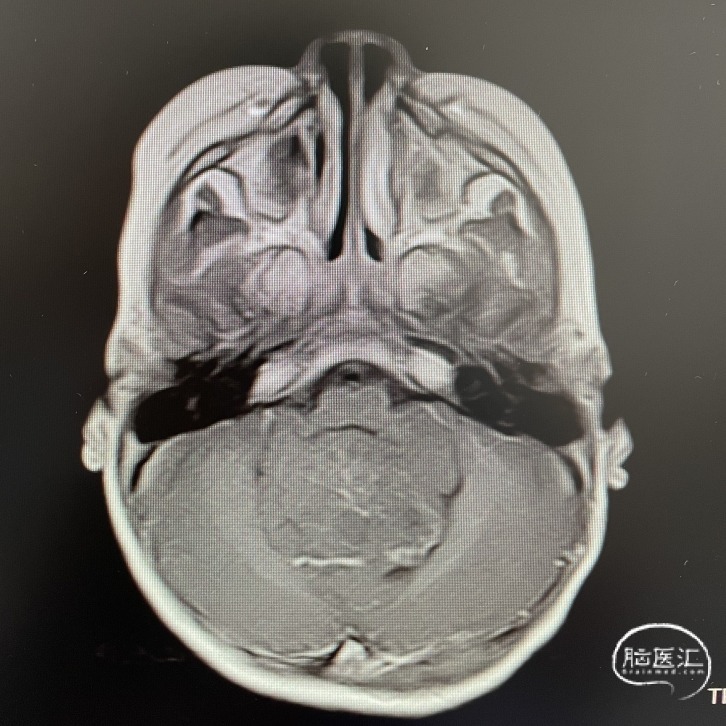

影像学资料

头部MRI检查:第四脑室扩大,其内可见一类圆形肿块,呈稍长T1稍长T2信号,边界清楚,较大截面范围约47*35*48mm。增强后呈不均匀强化;病灶向下延伸至颈段椎管内,向两侧孔延伸至桥小脑角区。幕上脑室系统扩大,周围可见片状长T1长T2信号。